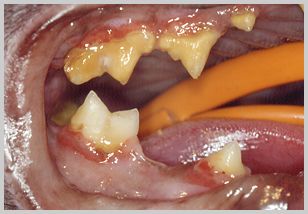

Advanced feline periodontal disease case which may include FORL's

The extraction techniques for cat teeth in the main follow those of dog teeth. Exceptions exist where subgingival resorptive lesions (FORL's or "neck lesions") damage teeth roots. Teeth affected by FORL's rarely have a morphologically intact root for extraction. In these circumstances, amputation of the crown and the root tissue, immediately below the alveolar bone crest, may be permissible.